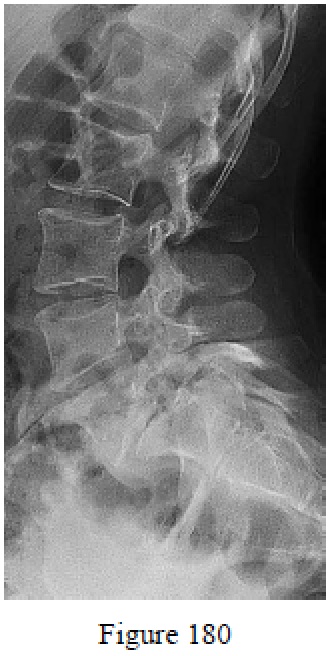

Question 180

Figure 180 is the lateral radiograph of a 17-year-old girl who has chronic low-back pain. She has normal motor examination findings but diminished light touch vs sensation in a L5 distribution. Her pain is reproduced with lumbar extension. Which morphologic parameter has been correlated with her spinal condition?